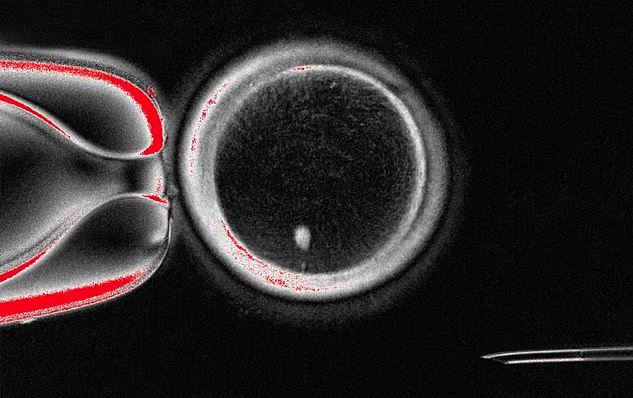

Në kuadër të studimit, shkencëtarët krijuan 82 vezë të tilla artificiale në laborator, nga të cilat rreth 9% u zhvilluan deri në fazën e blastocistit, një fazë e hershme e embrionit. Kjo është një arritje premtuese, edhe pse shumica e vezëve të fekonduara nuk përparuan më tej dhe disa prej tyre kishin anomali kromozomale.